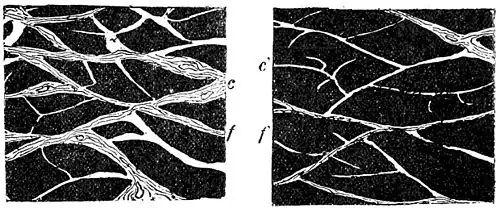

| Fig. 1.—Bruised Muscle without Massage. f, muscular fasciculus; c, intermuscular connective tissue. | Fig. 2.—Bruised Muscle with Massage. f, muscular fasciculus; c', intermuscular connective tissue. | ||

Fig. 2 shows that the natural size of the intermuscular connective tissue has been preserved, while Fig. 1 shows the intermuscular tissue thickened, and the muscular bundles thinner and compressed. (From the Archives générales de Médecine, Fevrier, 1892, p. 197.)